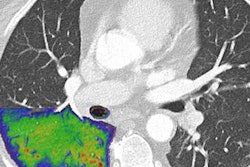

Wradzidlo and colleagues compared image quality and radiation dose between a dual-energy CT (DECT) device and a photon-counting CT scanner. Their study included 70 patients who underwent abdominal, contrast-enhanced CT between November 2021 and February 2022. The patients had both a DECT exam and a follow-up exam with a photon-counting device (median time between the two scans was four months). The researchers assessed radiation dose between the two types of studies using the following metrics: CT dose index, dose length product, and size-specific dose estimation. Two radiologists scored the images for quality, particularly lesion visibility.

The group found that photon-counting CT reduced the size-specific dose estimation by 32%, without degrading image quality.

Additionally, the two readers rated lesion conspicuity higher on the photon-counting CT exams compared with the DECT exams, especially in the third quartile, the team noted.